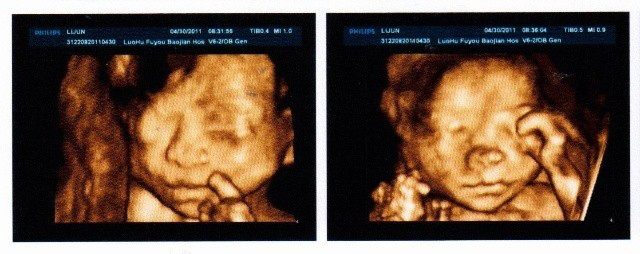

各位大姐帮忙看下宝宝四维彩超头像鼻子正常吗?

图片尺寸384x288

孕妇做四维彩超胎儿鼻子扁又大胎儿也是有苦说不出啊

图片尺寸940x695